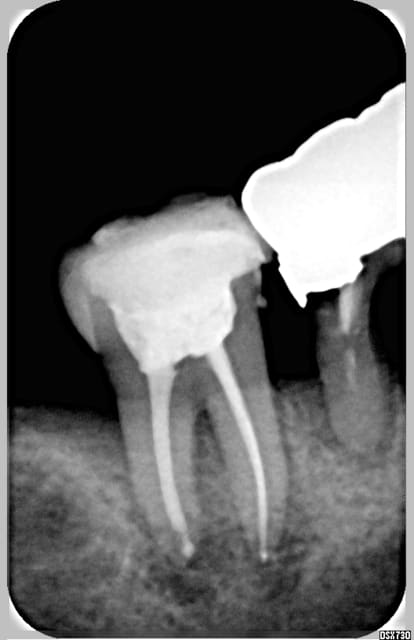

à la radio, on voit rien sauf une alvéolyse plus prononcée en regard de la dent mais rien d'hyper flagrant.

A la radio, on voyait un peu d'alvéolyse, consécutive surement à ce tissu.

tonio, il faut que tu nous montre une radio.

si tu as un os interradiculaire à peu près convenable, avec un peu d'os en apical, pour une stabilité primaire, l'implantation immédiate aurait été possible, en visant bien entre les trois alvéoles.

En tout cas, en curetant l'alvéole, je n'avais pas l'impression qu'il y avait beaucoup d'os inter radiculaire. Par contre, l'alvéole était bien profonde et il y a eu un bon saignement après l'extraction et un beau coagulum qui s'est formé.